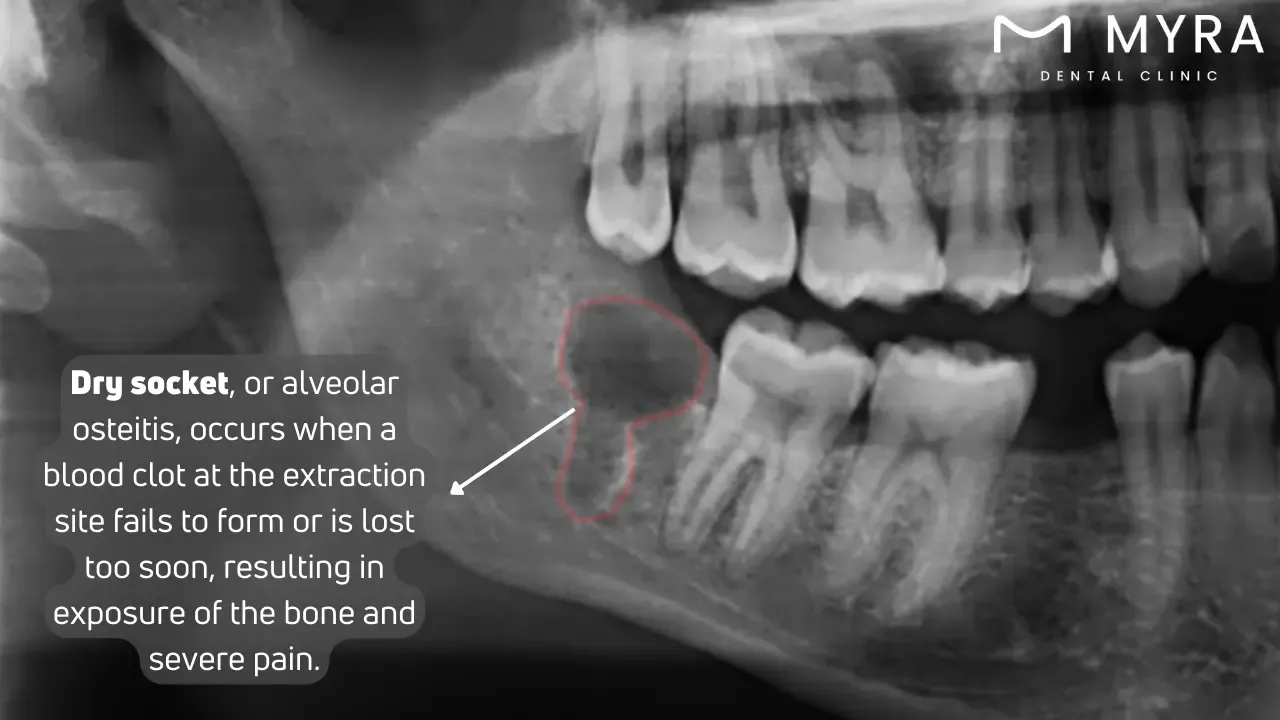

A dry socket, medically termed alveolar osteitis, represents a common yet painful complication following tooth extraction. A blood clot normally forms within the empty socket, the void left in the bone, as the body begins to heal after a tooth is removed. The clot protects the underlying bone and nerves from exposure to air, food particles, and fluids, facilitating proper healing. The protective blood clot does not form adequately or is dislodged too soon, leading to severe pain and complications in dry sockets.

A dry socket, medically termed alveolar osteitis, represents a common yet painful complication following tooth extraction. A blood clot forms within the empty socket, the void left in the bone, as the body begins to heal after a tooth is removed. The blood clot protects the underlying bone and nerves from exposure to air, food particles, and fluids, facilitating proper healing. The clot essentially acts as a biological dressing, promoting tissue regeneration and preventing contaminants from entering the wound site.

The protective blood clot does not form adequately or is dislodged too soon in cases of dry sockets. What does dry socket look like? It appears as an empty-looking socket with exposed bone, with a whitish appearance due to the bone being visible. The premature loss of the clot exposes the bone and nerves, resulting in severe pain that radiates to the ear, eye, or neck on the same face as the extraction.